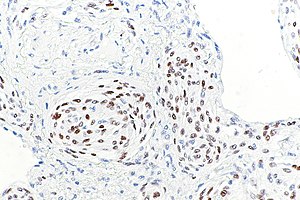

PR staining in pulmonary meningothelial-like nodule. | |

| Positive | many breast carcinomas, pulmonary meningothelial-like nodule |

- Pulmonary meningothelial-like nodule.